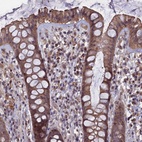

Immunohistochemical staining of human rectum shows moderate cytoplasmic positivity in glandular cells.